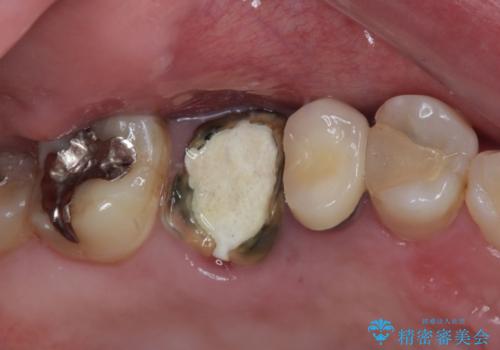

- 近医にて治療がなかなか進まないとのことで来院された患者様です。

詰めている材料を外したところ、目視で確認できるほど割れており、要抜歯との説明をし、インプラント治療を行うこととしました。